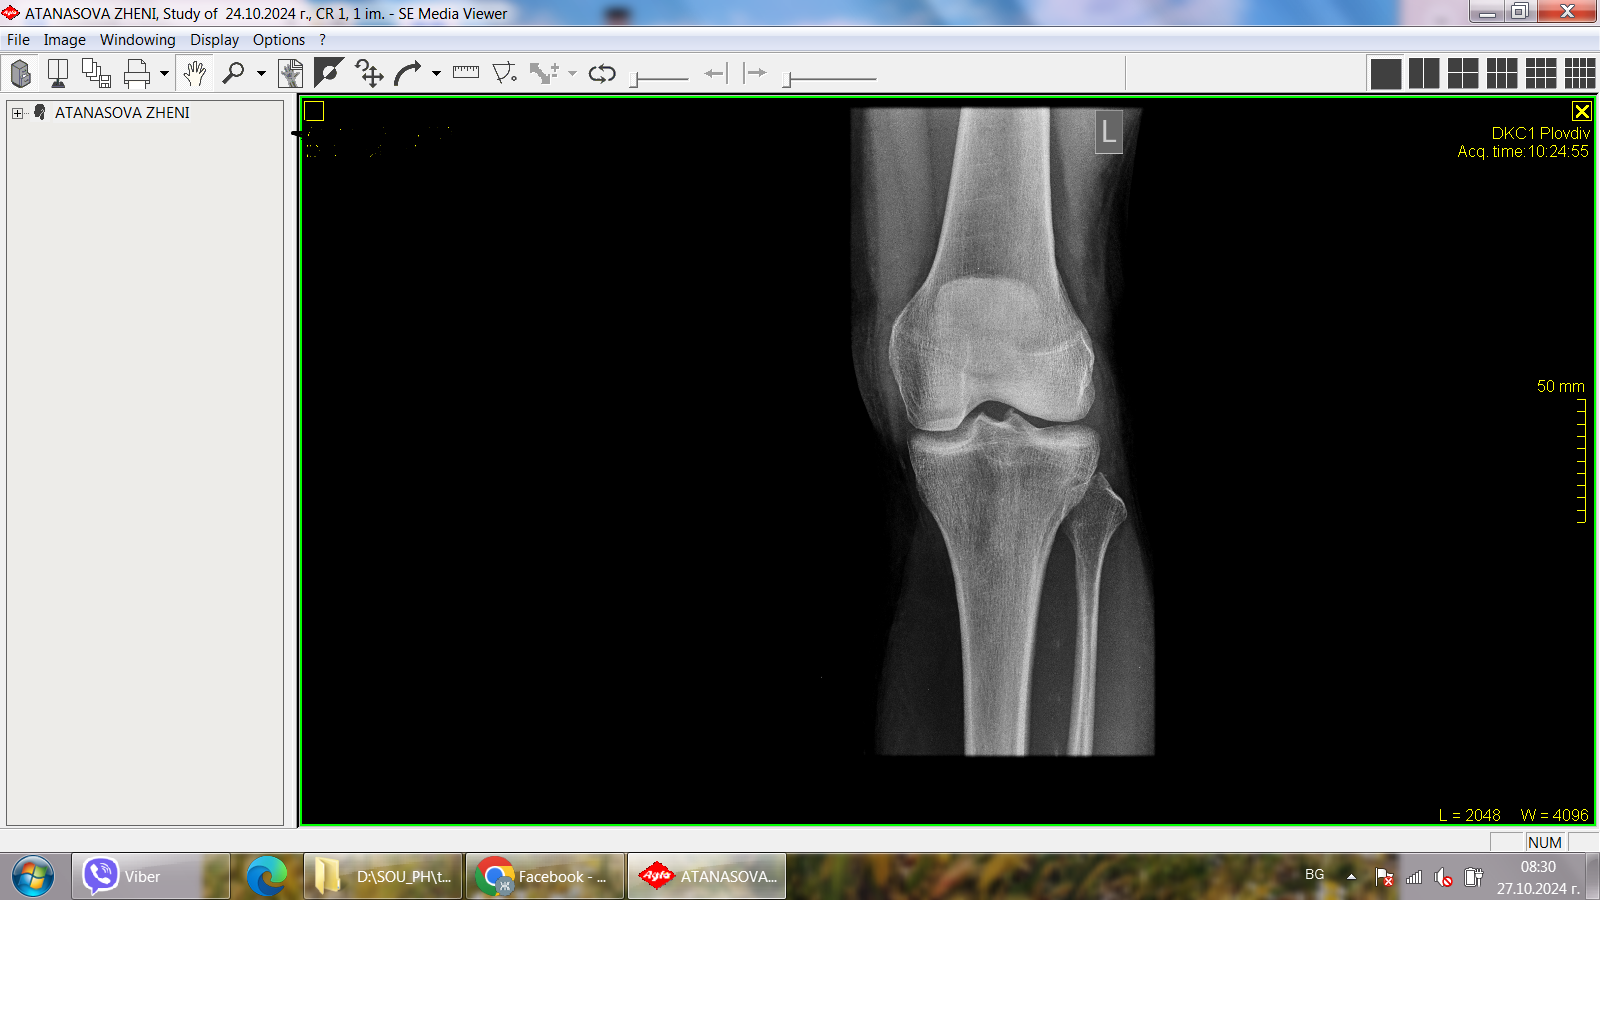

Да се направи рентгенография - профилна проекция.